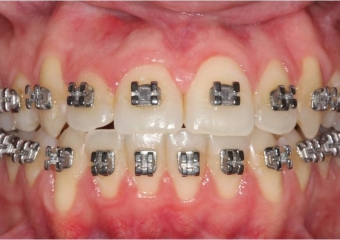

Mordida inicial

Mordida após a cirurgia